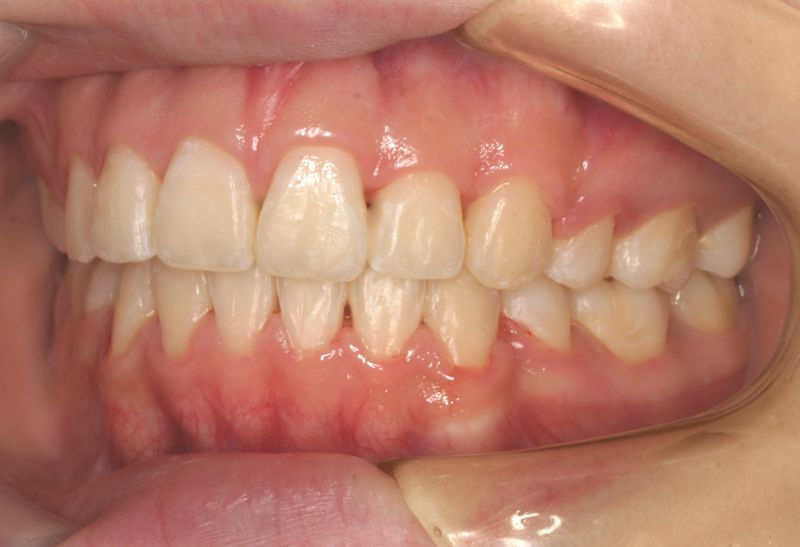

Case 3

主訴:  八重歯が気になる。

診断:  アングルⅠ級 叢生

治療方針:

患者さんは19歳の男性であった。上下顎左右側犬歯の低位による審美障害を訴えた。第一大臼歯はⅠ級の咬合様式であったことから上下顎左右側第一小臼歯の抜歯とホールディングアーチによる加強固定を行い、セクショナルアーチを用いて上下顎左右側犬歯を歯列内に誘導し、咬合関係の改善を図ることとした。

治療期間: 1年3カ月

費用:

診断費30000円、装置費用600000円、保定装置費用50000円、月1回の調整費4000円  (全て税別)

【 治療前 】

【 治療後 】